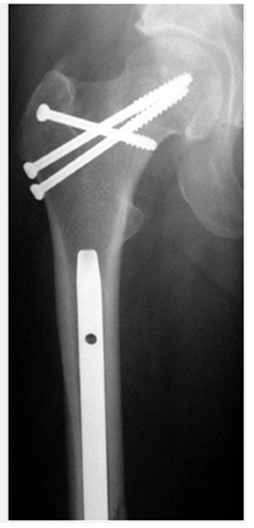

شكستگي گردن فمور همراه با شفت فمور . شكستگي گردن فمور با سه عدد پيچ و شكستگي شفت فمور با نيل رتروگراد فيكس شده است.